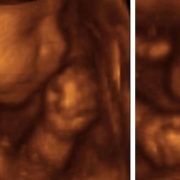

La grossesse extra-utérine caractérise une grossesse qui va se dérouler à l’extérieur de l’utérus. Le plus souvent, l’oeuf va s’implanter dans l’une des deux trompes, très rarement au niveau du col de l’utérus, sur un ovaire ou dans la cavité abdominale. C’est un cas de grossesse rare

Dans une grossesse normale, l’ovule vient se nicher à l’entrée des trompes. Les spermatozoïdes libérés remontent jusqu’aux trompes pour féconder l’ovule. L’œuf va ensuite descendre la trompe pour se fixer dans la paroi de l’utérus. Dans le cas d’une grossesse extra-utérine, la nidification a lieu dans la trompe. Mais l’œuf lorsqu’il va commencer à se développer va manquer de place dans la trompe, au risque ensuite de faire éclater la trompe.